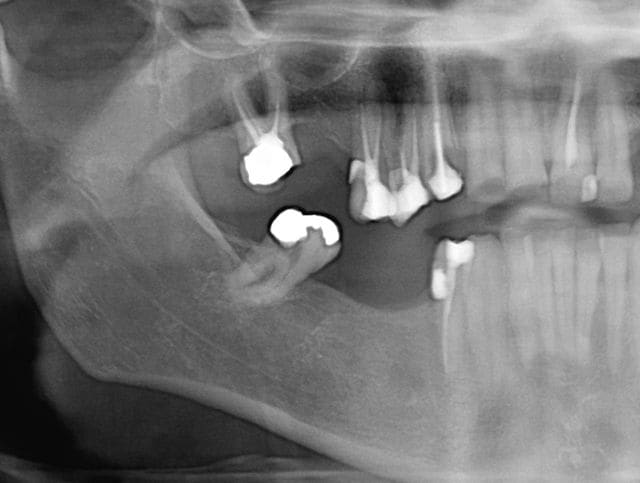

Tiens puisque c'est la journée des courbures, l'endo de ce soir. Protaper tout con aussi (digue, cathétérisme, S1, S2, F1, F2, gutta condensor) sur 48 (47?) 2 canaux, CMU.

edit : il est prévu de couronner cette dent, dans le cadre d'un relèvement général de la DV, sur la radio c'est un simple pansement + l'ancien amalgame distal. merci de votre lecture !